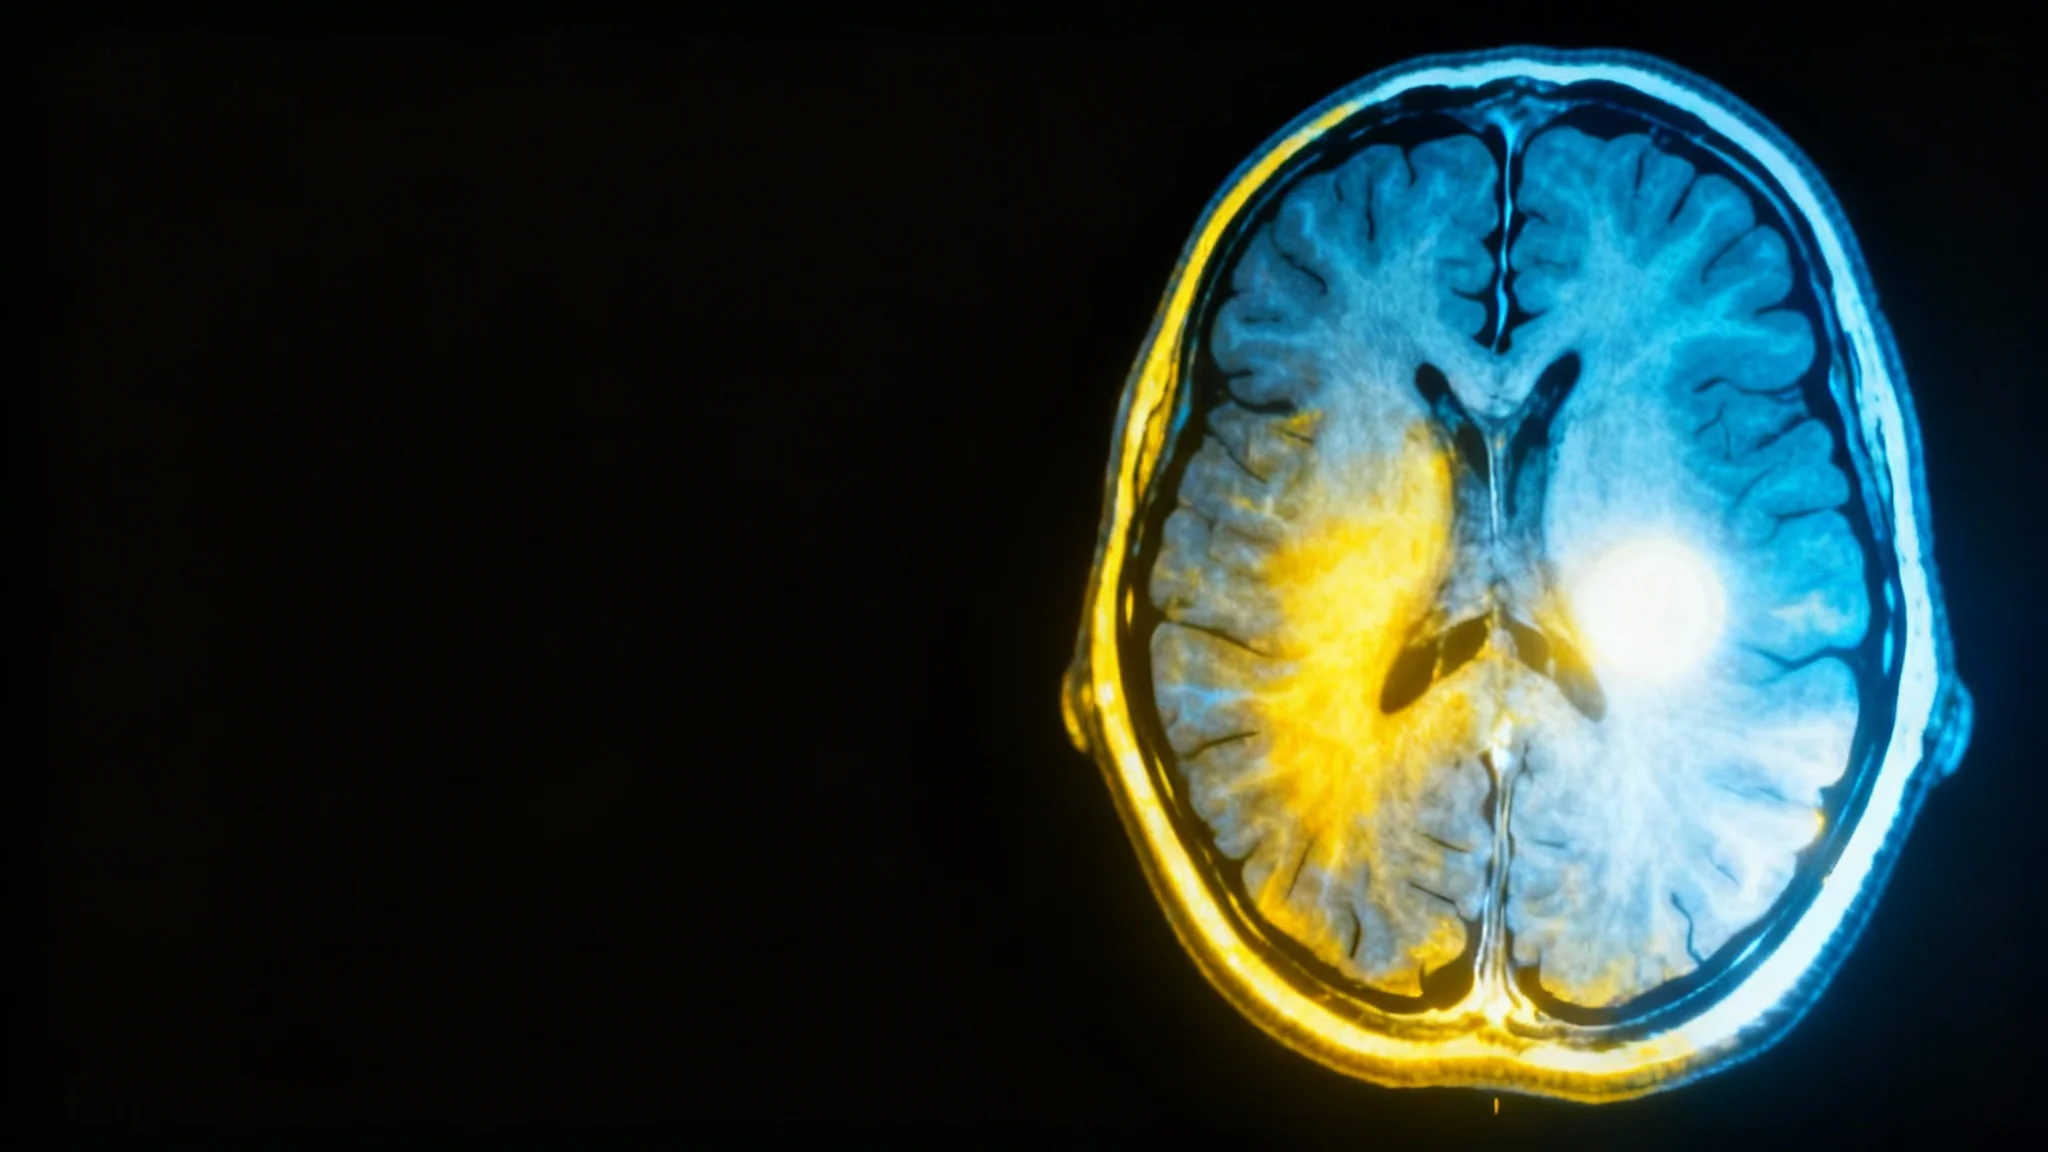

A highly detailed and enhanced 16:9 MRI scan of a human brain, showing specific regions illuminated with a vibrant color gradient to indicate high contrast and signal intensity.

AI-Powered MRI Contrast Enhancement

Improve the clarity of MRI scans with AI. Enhance contrast to sharpen anatomical details and improve the definition of pathological findings.

Our AI tool sharpens the details that matter most in medical imaging. By enhancing the contrast of MRI scans, it helps to better delineate the boundaries of tumors, define the extent of inflammatory processes, or clarify subtle tissue variations. This improved visual clarity can support radiologists and clinicians in making more confident diagnostic assessments. The technology works to amplify key features within the image, turning ambiguous scans into more definitive studies. Upload your scan to see how AI can help refine your interpretation and analysis.